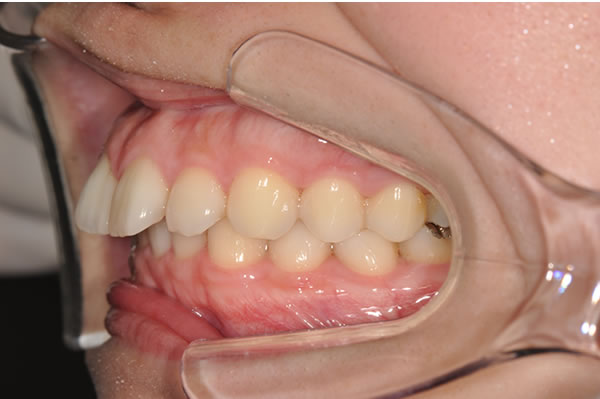

上顎前突症(出っ歯)の矯正症例 ケース02

| 治療前(初診) | 治療後 | |